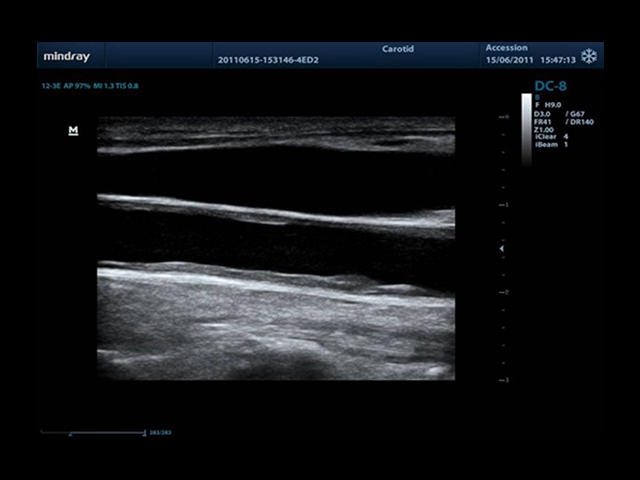

Mindray DC-8 Exp – это ультразвуковой аппарат с архитектурой mQuadro и функцией эластографии Natural Touch. Он оснащен высококлассным 21-дюймовым TFT-монитором с разрешением Full HD. Данный аппарат представляет интерес для специалистов, занимающихся обследованием мягких тканей с использованием эластографии. Режим объемного 4D-сканирования позволяет получать максимально точные диагнозы, сокращая количество неэффективных процедур.

Mindray DC-8 Exp оснащен новым поколением датчиков с увеличенным количеством элементов и инновационной технологией "3T". Это позволяет достичь высокой детализации и качества изображения. Благодаря новейшей технологии iFlow, можно визуализировать даже самые мелкие сосуды и кровеносные пути.

Сверхширокополосная нелинейная обработка изображений снижает визуальные шумы на 30% по сравнению с другими системами. Технология iClear позволяет устранить зернистость изображения, а iBeam (технология пространственного компаундинга) обеспечивает высокое качество сканирования органов и тканей под различными углами.